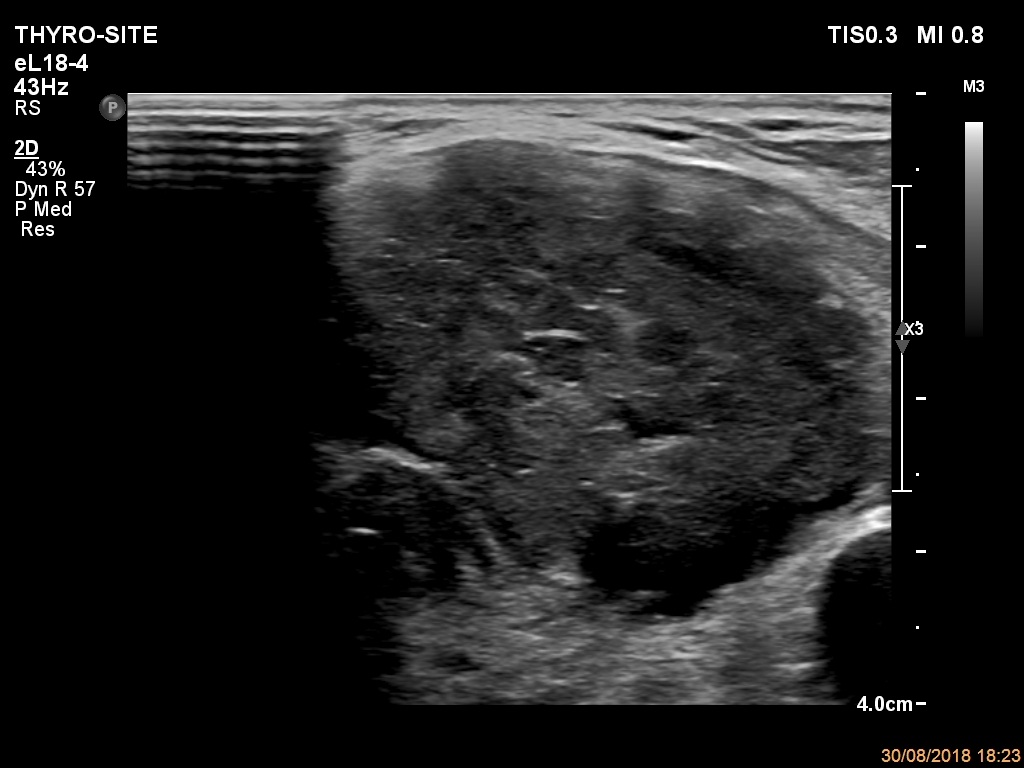

Ultrasonography. The thyroid was echonormal. There were a few hypoechogenic areas in the right lobe. There was a hypoechogenic mass with irregular shape in the left lobe. The lesion had echonormal fields and connective tissue. The microflow imaging revealed no intranodular vascularization while the lesion proved to be very hard on elastography.